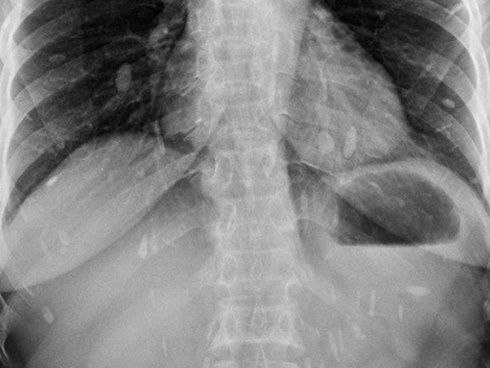

Hình ảnh sán lá gan